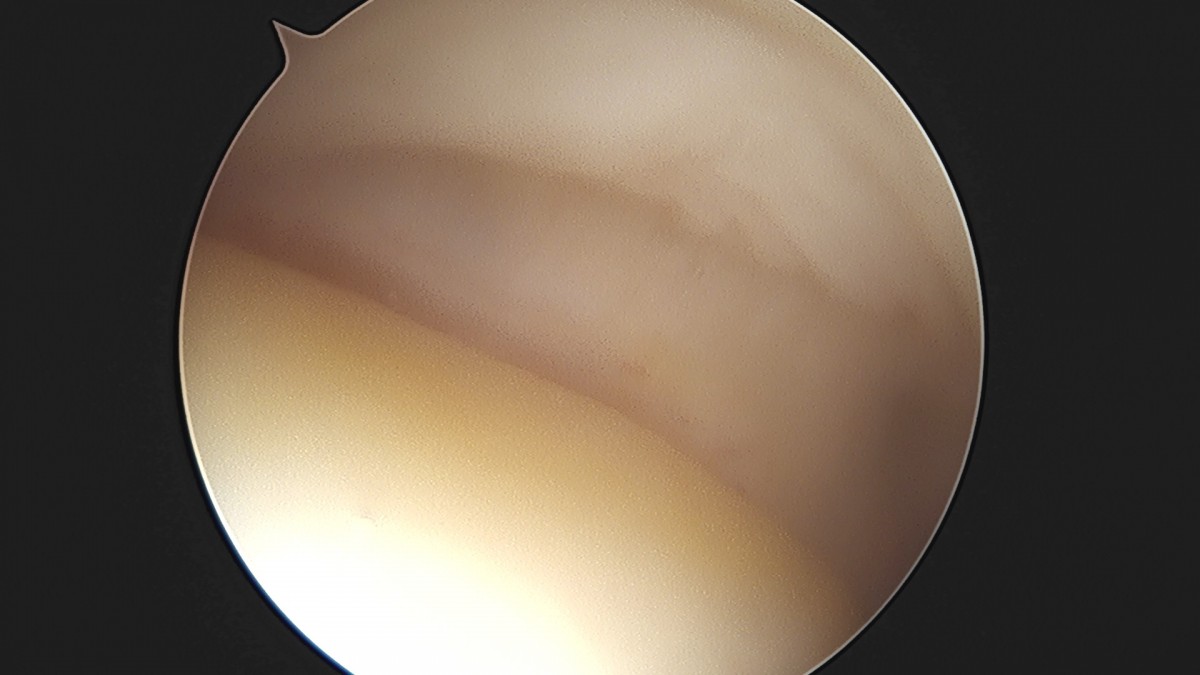

이재상원장님 어깨 견봉하 감압술 및 석회 제거술 이형O 환자

작성자 최고관리자 댓글 0건 조회 746회 작성일 25-09-16 15:40